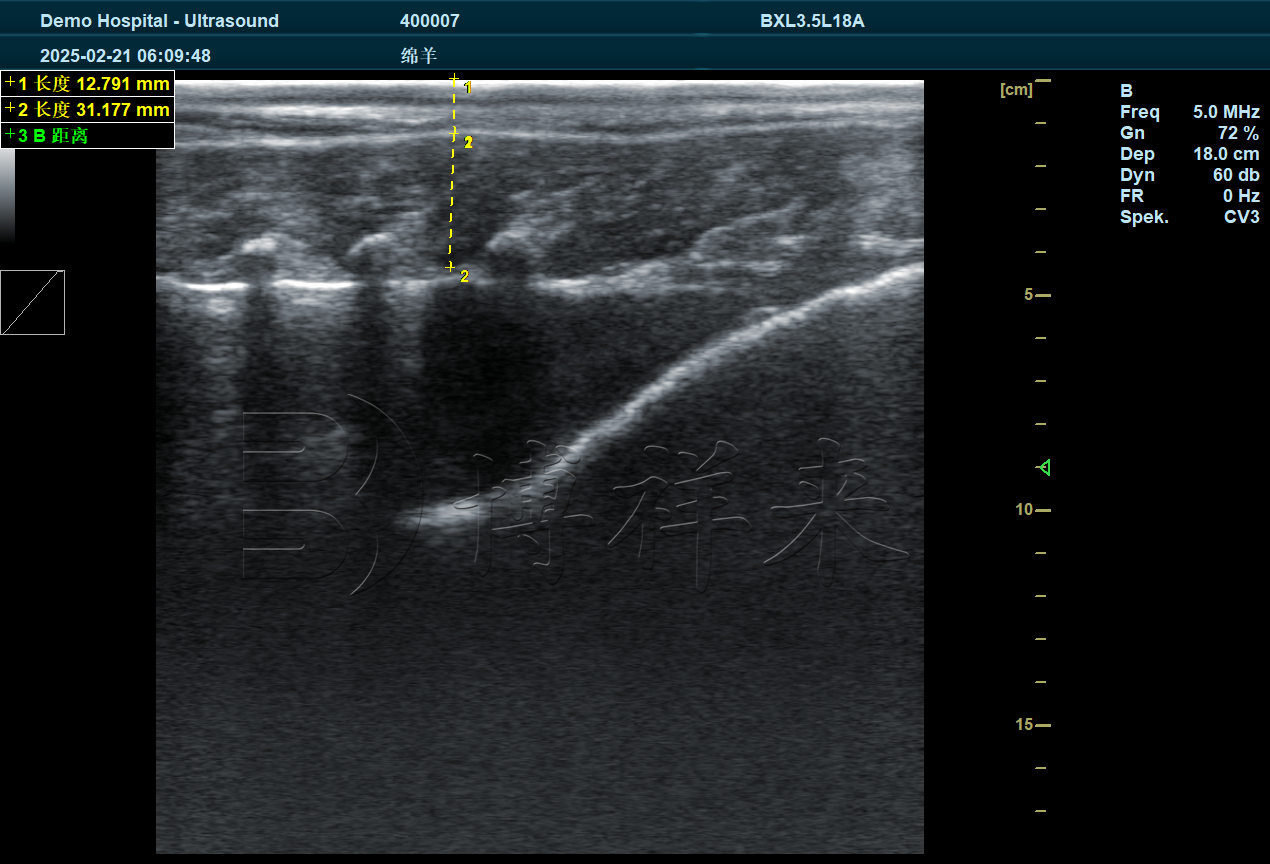

优质的羊背膘仪图像应能看到:皮肤层 → 脂肪层 → 肌肉层三层结构。

将探头垂直贴在第 12–13 肋间位置,让图像横截面显示背部肌肉结构。羊的背膘层通常呈均匀浅回声,肌肉层呈纤维状中等回声,界限清晰。

4. 测量背膘厚度与眼肌宽度

羊背膘仪大多具备自动测量功能,只需点选图像上脂肪层的上下边界即可自动获得数据。